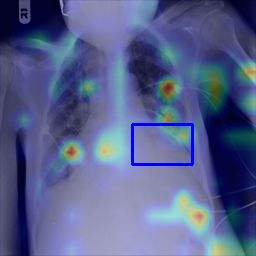

Deployments of artificial intelligence in medical diagnostics mandate not just accuracy and efficacy but also trust, emphasizing the need for explainability in machine decisions. The recent trend in automated medical image diagnostics leans towards the deployment of Transformer-based architectures, credited to their impressive capabilities. Since the self-attention feature of transformers contributes towards identifying crucial regions during the classification process, they enhance the trustability of the methods. However, the complex intricacies of these attention mechanisms may fall short of effectively pinpointing the regions of interest directly influencing AI decisions. Our research endeavors to innovate a unique attention block that underscores the correlation between 'regions' rather than 'pixels'. To address this challenge, we introduce an innovative system grounded in prototype learning, featuring an advanced self-attention mechanism that goes beyond conventional ad-hoc visual explanation techniques by offering comprehensible visual insights. A combined quantitative and qualitative methodological approach was used to demonstrate the effectiveness of the proposed method on the large-scale NIH chest X-ray dataset. Experimental results showed that our proposed method offers a promising direction for explainability, which can lead to the development of more trustable systems, which can facilitate easier and rapid adoption of such technology into routine clinics. The code is available at www.github.com/NUBagcilab/r2r_proto.